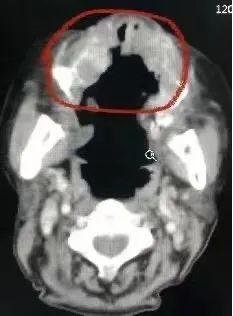

患者CT图,治疗一次后

采访时,正值宋奶奶接受第二个周期的最后一次治疗,王女士表示,相比刚入院时,老人的精神要好很多。肿瘤脱落后原本没有长肉的地方也在慢慢恢复,休养了3个月,长了10斤肉。现在看ct报告,肿瘤几乎消失了。虽然现在老人还不能吃大块的食物,但是可以吃米饭了,也能吃到味道了。“能恢复到现在这样,我真的没想到。”